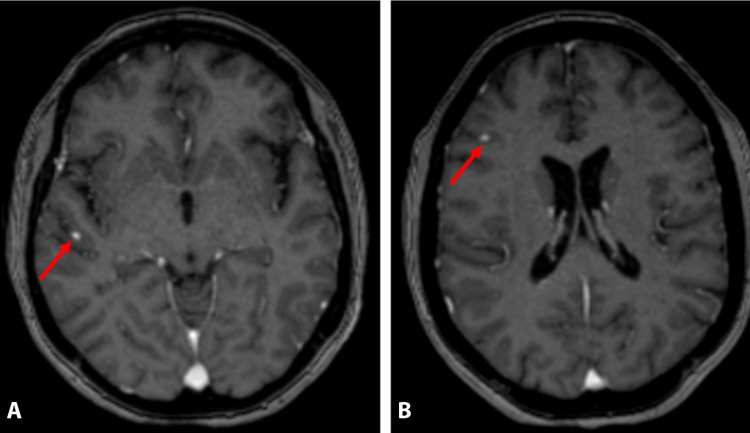

Magnetic resonance (MR) imaging showing a few leptomeningeal micronodular lesions (Fig. 1 ). A 43-year-old woman was referred with complaints of severe headache, cough, and fever. The patient had systemic lupus erythematosus disease for ten years. Her body temperature was measured as 38.6 °C. Laboratory findings revealed mild leukocytosis (WBC = 12,450/mm3). Real-time reverse-transcriptase-polymerase chain reaction (rRT-PCR) was positive for COVID-19. Thorax computed tomography (CT) showed common ground glass densities in both lung parenchyma. Magnetic resonance (MR) imaging showed a few leptomeningeal micronodular lesions (Fig. 1). The lupus patients may be more susceptible for a more severe COVID-19 disease course [1]. CT scans appear sensitive virus detection [2].

Fig. 1.